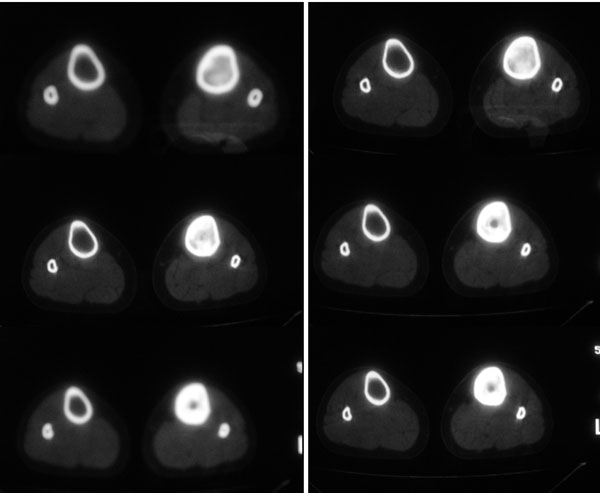

以下是引用卜一在2007-11-12 5:56:00的发言:[br]胫骨中上段骨内外膜增生,骨质硬化,部分骨皮质增厚,髓腔高度变窄,界限不清。多考虑:1 慢性低毒性感染。2 不除外骨纤维异常增殖症!